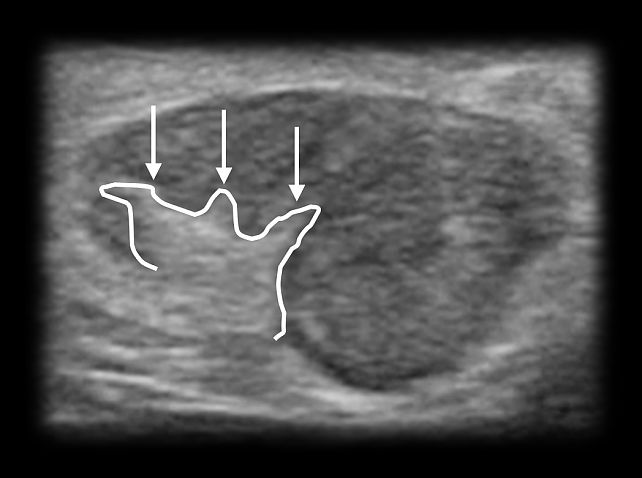

- Corticomedullary interface distortion: irregularity in the normally clear boundary between cortex and medulla (Figure 8).

8

Distortion of the lymph node corticomedullary interface (arrows).